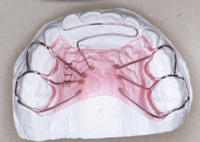

叢生(前歯のデコボコ) 8歳女子

治療前

治療後

①主訴:前歯の不揃いを治したい

②診断名あるいは主な症状:前歯部の叢生(アゴと歯の大きさの不調和)

③年齢:8歳

④治療に用いた主な装置:ライトワイヤー法

⑤抜歯部位:非抜歯

⑥治療期間:約1年半

⑦治療費:検査:38,500円

基本矯正費用:440,000円~

調整料:6,600円 (ひと月に1回)

⑧リスクと副作用:治療開始後数日は噛むときに痛みがあります。

虫歯予防のため適切な歯磨きが必要

装置が破損することがあるため、その時は連絡をすること

後戻り防止のため、保定装置の装着が必要である。

第2期(永久歯列期)での仕上げの治療が必要になる場合もある